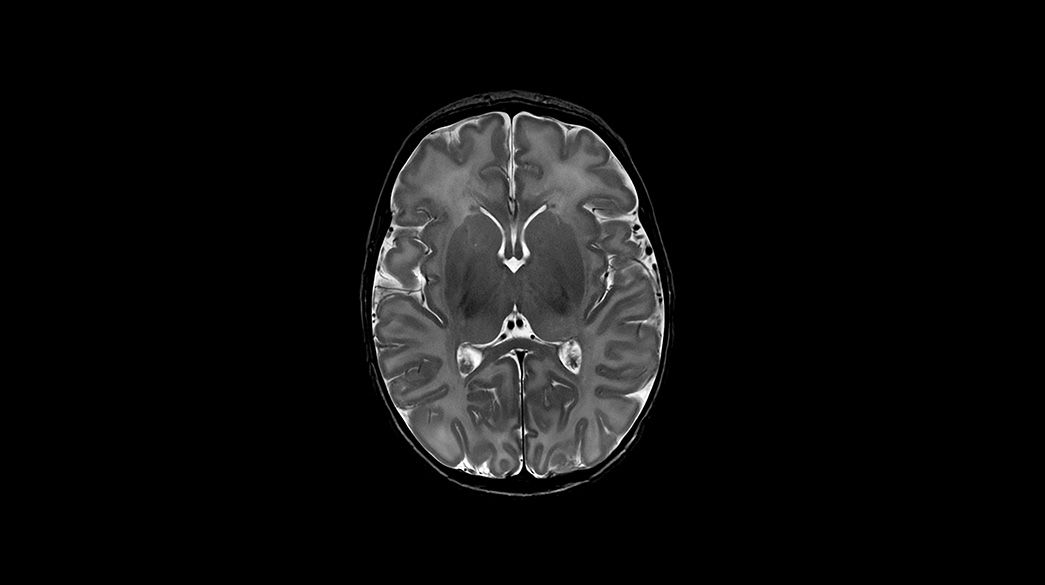

Pediatric MRI for SIGNA™

Specialized pediatric MRI protocols specifically designed to meet the needs of your smallest, most fragile patients. Provide ease of use for technologists and clinical excellence for clinicians.

Clinical Pediatric MRI

Pediatric MRI imaging applications

Precision and personalization